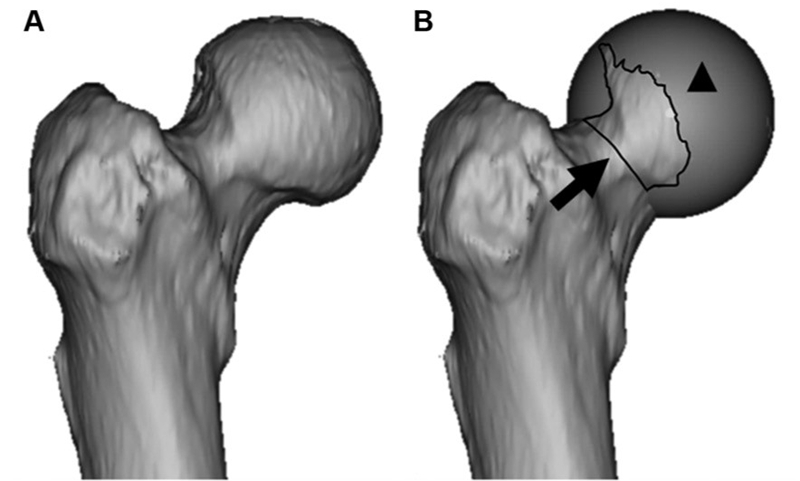

当前,髋关节成形操作尚无统一的评价,大多数患者对于FAI患者股骨侧Cam的评估及成形后评估均依赖于X片和三维CT进行主观评价。髋关节成形不足导致髋关节镜术后骨性撞击残留是患者髋镜手术效果不佳甚至需行髋关节镜翻修手术的最常见原因之一。陈疾忤教授[2]曾经报道基于三维CT下球形模拟法标记股骨Cam的大小和范围,使得术者在髋镜术前对患者的Cam的评估更加精准,提高髋镜术中Cam成形的精度。在对于髋镜翻修手术时,初次髋镜手术所进行的磨骨成形增加了翻修手术时镜下识别、定位Cam部位更的困难度,利用Carbone等[3]3D软件标记出残留的Cam,提高了髋镜翻修手术髋关节成形的精度。

图1:球形模拟标记股骨Cam

图2:3D软件在髋镜翻修手术前标记残留的Cam